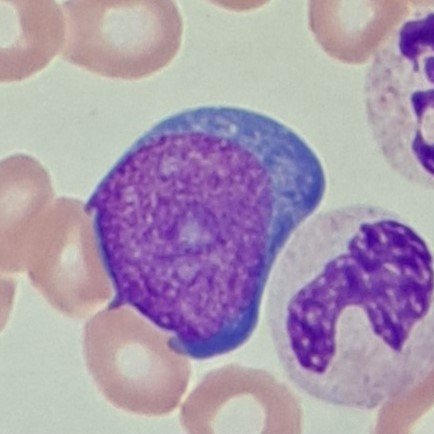

Mesothelial cells are described as having a “fried egg” appearance. They have a round to oval nucleus with smooth borders and evenly distributed chromatin. Nucleloli are usually present. Mesothelial cells may also be multinucleated.

Macrophages are about the same size as mesothelial cells, so the two can often be confused. Macrophages can usually be differentiated by the presence of vacuoles and a lacey chromatin. If both cell types are present and differentiation is difficult, take a look around the slide to get an idea of each kind of morphology before starting a differential.